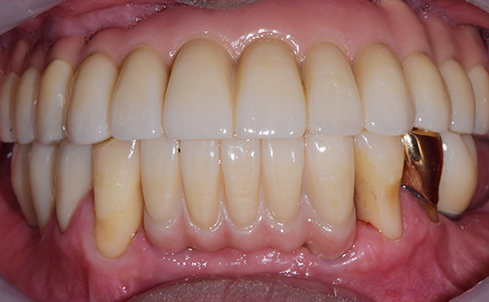

Fully edentulous clinical cases